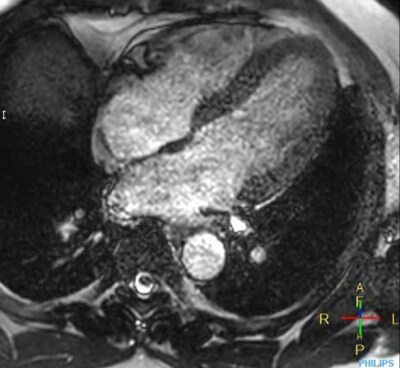

Cine 2D BFFE (4 CAV)

Elition X 3.0T

Hospital Metropolitano de la Policía de Tokio, Japón